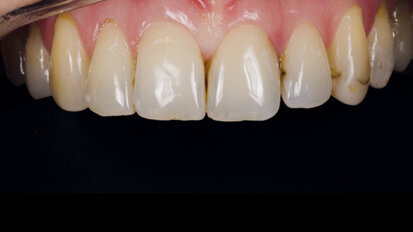

Nový úsměv za jeden den

Čt. 28. května 2020